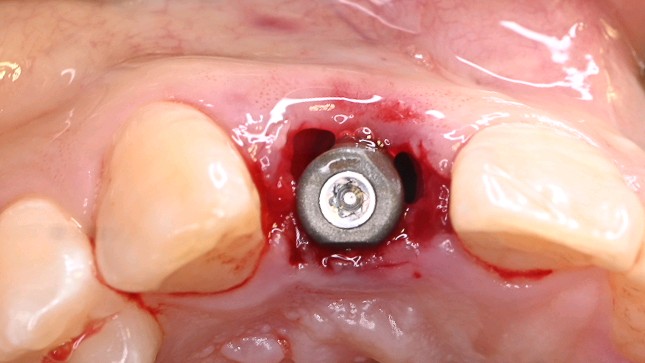

c、即刻植入根据拔牙窝的位置方向和颌骨的解剖形态,将钻头方向贴着腭侧骨板,采用逐级备洞的方法制备种植窝,植入适当长度和直径的种植体。即刻修复如种植体初期稳定性≥35N/ cm ,可行即刻修复。术中行数字化无痛印模,送工厂行高精度义齿制作,1周内复诊,行义齿戴入,所有即刻修复体均调整至正中、前伸和侧方咬合均无接触。根据种植愈合情况,即刻修复3-6个月后再行永久修复

3.5倍显微镜下拔牙,刮囊肿,植入ITI 种植体。

数字化无痛印模1min

加工厂制作临时修复体

戴牙